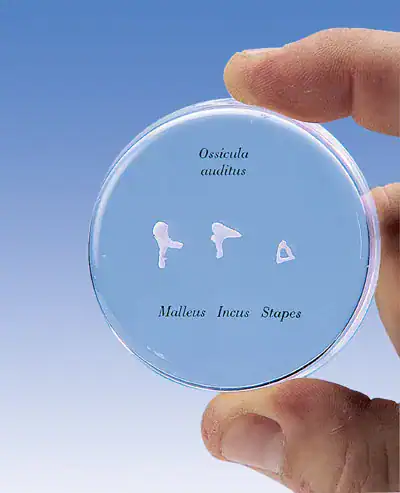

1000200

Torso tweeslachtig met open rug 28-delig